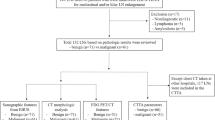

We identified a total of 63 CTs demonstrating lymphadenopathy and sufficient clinical data for categorization during the study period, including 34 patients with malignant lymph nodes and 29 patients with benign lymph nodes (secondary to appendicitis or inflammatory bowel disease). Mediastinum and retroperitoneum were the most common sites for malignant lymphadenopathy in this study cohort (7 cases each), while mesenteric lymphadenopathy constituted a significant majority of the cases of benign lymphadenopathy (19 cases). The overall study cohort comprised 40 males and 23 females, with average ages of 12.4 years and 12.1 years at the time of CT acquisition in the malignant and benign groups, respectively. Patient demographics and underlying diagnoses are summarized in Table 1. Mean follow-up of the patients in the benign group was 30.8 months.

Finally, we compared the performance of CT textural analysis to the performance of mean lymph node Hounsfield unit (HU) attenuation value without TA for determining lymph node malignancy. Based on ROC analysis of the unfiltered lymph node data, the optimum CT attenuation threshold for detecting malignancy was a mean HU threshold greater than 29.8, which yielded 100% sensitivity, 6.9% specificity and 57.1% accuracy (Table 4). The specificity and accuracy performance of the TA-derived threshold values, both based on the unfiltered and filtered image data, were both statistically superior to the non-TA-based attenuation threshold (P<0.05, McNemar test, Table 4). To illustrate the varying outcomes, individual cases assessed using mean lymph node HU alone, which demonstrate true-positive, true-negative, false-positive and false-negative results compared to tissue diagnosis, are shown in Fig. 2.

Sample application of textural analysis in cases of benign and malignant lymphadenopathy on axial contrast-enhanced CT images. Right paratracheal lymphadenopathy in a 10-year-old boy (a) and portocaval lymphadenopathy in a 14-year-old girl (b), both with Hodgkin lymphoma. Mesenteric lymphadenopathy in a 7-year-old boy (c) and a 6-year-old girl (d), both with acute appendicitis. A Hounsfield unit (HU) value of 79.2 was the threshold used when textural analysis (TA) was applied to distinguish benign from malignant lymphadenopathy. FN false negative, FP false positive, TN true negative, TP true positive